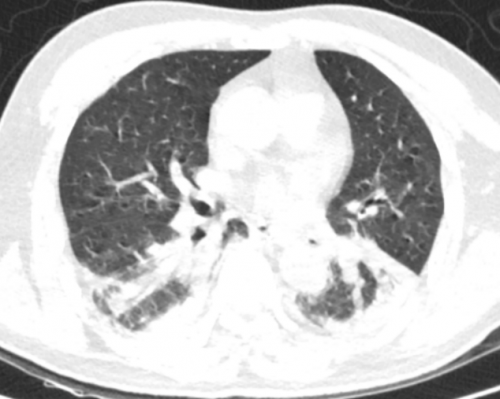

11月22日肺部CT

两肺渗出性改变,较前片两肺渗出进展、两肺下叶实变范围增大。